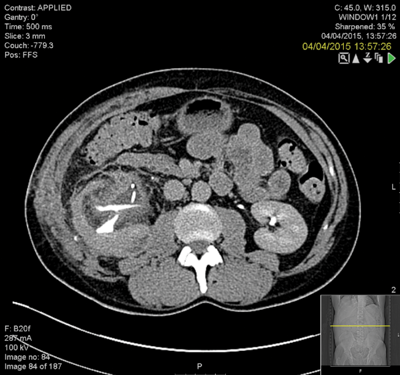

The kidney was grossly inflamed and it was very difficult to identify the anatomy. The surgeon considered a nephrectomy but persevered to complete the repair. The patient remained in hospital for two weeks postoperatively with low grade pyrexia and a CT revealed a clot in the collecting system and possible calyceal perforation (Figure 4) and extravasation. This was seen to have improved on a subsequent CT (Figure 5).

Figure 4.

Figure 5.